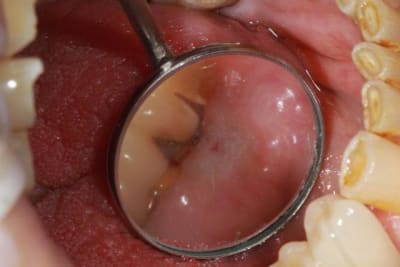

alors là pas du tout, le patient vient me voir pour des implants, donc je fais une étude du cas absence des molaires supérieures, couronnes mandibulaires très ancienne 45 racine cassée, 44 dévitalisée mais passablement déchaussée, donc avulsion de 45 et pose d'un implant avant de refaire les couronnes 46/47 et l'ensemble.

mettre 3 screw-posts dans les racines de la 6 ce n'est pas du sur-traitement c'est un assassinat dentaire !

suis pas sur du tout que ce soit un assassinat , 2669 .

pourtant je ne suis pas fan des screw-post loin de là !

mais la reconstruction est bien gerée , le cd ç est bien battu pour cette 6 .y a pas de quoi appeller hercules poirot .

j'ai choisi la moins mauvaise solution, fonction de ce que je sais faire, 3 screws post scellées, et résine...pas top mais ça ne mérite pas la chaise électrique.

Bien sur j'aurais gagné plus en faisant un IC à clavette, comme à la mutuelle... mais pour avoir passé 1h30 et cassé 8 fraises sur le dernier IC clavette que j'ai déposé, j'évite ce genre de travail.